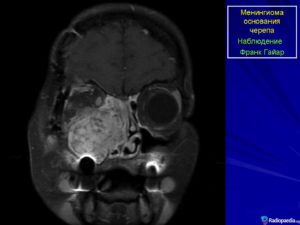

Менингиома располагается вдоль основания черепа и оболочки венозных синусов. Очень часто она встречается в парасагиттальном синусе, затылочном отверстии, в области больших полушарий мозга и мостомозжечковом углу.

Наиболее часто внутричерепные менингиомы располагаются парасагиттально и на фальксе (25%). Конвекситально в 19% случаев. На крыльях основной кости — 17%. Супраселлярно — 9%. Задняя черепная ямка — 8%. Ольфакторная ямка — 8%. Средняя черепная ямка — 4%. Намет мозжечка — 3%. В боковых желудочках, большом затылочном отверстии и зрительном нерве по 2%.

При единичном дефекте удалить его намного проще, чем при вовлечении в патологические поражения сразу нескольких областей – обонятельная, ольфакторная менингиома. Склонность к подобной патологии имеют женщины, но иногда страдают и дети.

По локализации менингиомы:

- опухоль зчя – с поражением основания черепа;

- передней черепной ямки;